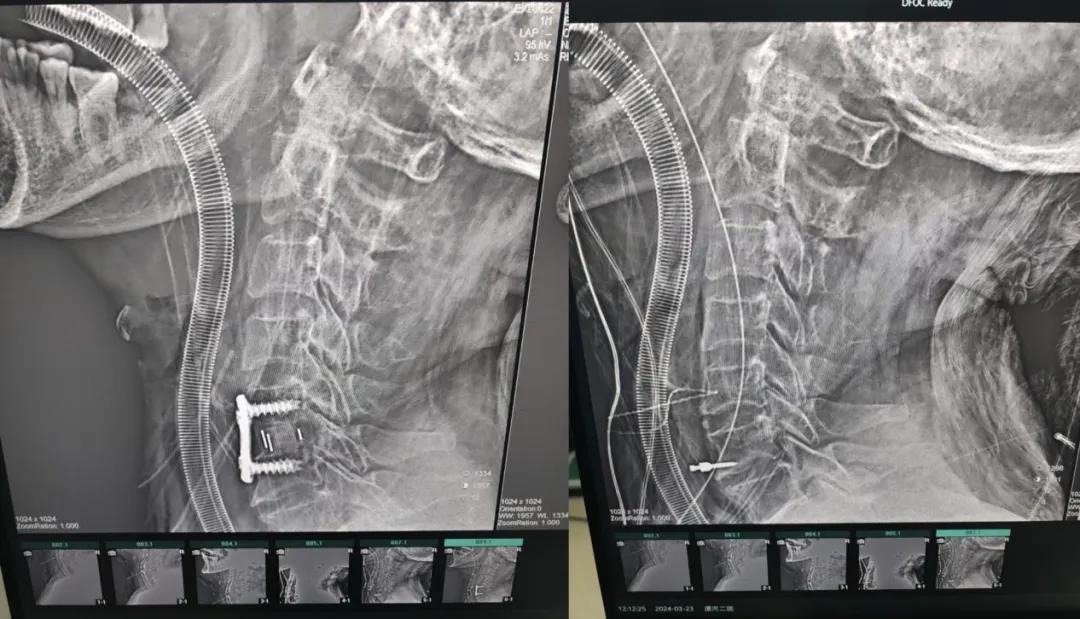

經(jīng)過(guò)縝密的術(shù)前準(zhǔn)備和手術(shù)計(jì)劃,在鄭大一附院神經(jīng)外科張風(fēng)江教授的指導(dǎo)下,神經(jīng)外科團(tuán)隊(duì)順利為患者實(shí)施“顯微鏡下頸椎前路C5/C6椎間盤切除椎間融合+內(nèi)固定術(shù)”,手術(shù)時(shí)間不到1小時(shí)。術(shù)后患者恢復(fù)情況良好。